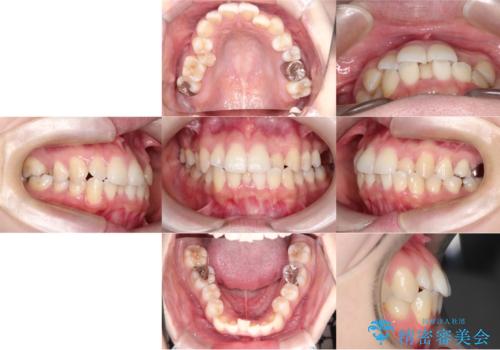

【ワイヤー矯正】口元を下げたい、下の歯の凹凸を無くしたい

- 主訴:口元を下げて前突感を無くしたい、下の歯の凹凸も無くしたい

右側第二小臼歯、左側第一小臼歯、下顎両側第一小臼歯を抜歯しワイヤ-矯正を行いました。

骨格的顎の変位を認めたため、顔貌に対しピッタリ上下の歯の正中を合わせることは難しいと説明し、上下左右計4本小臼歯を抜歯しワイヤー矯正治療を行いました。